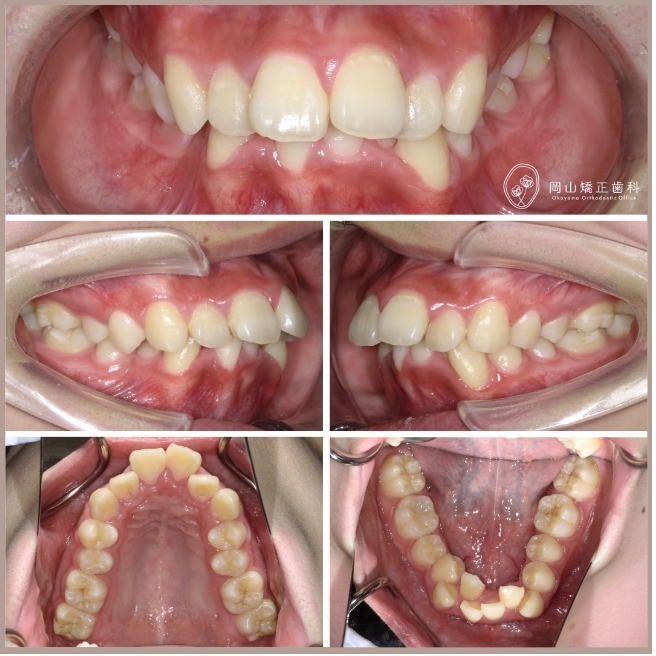

症例01

症例詳細

| 主訴 | 出っ歯が気になる |

| 診断名 | 叢生と過蓋咬合を伴う上顎前突症例 |

| 治療装置 | マルチブラケット矯正装置(ワイヤー矯正) |

| 抜歯部位 | 上顎両側第1小臼歯、下顎両側第1小臼歯 |

| 治療期間 | 2年11ヶ月 |

| 費用 | 約85万円 |

| リスク | 痛み、歯肉退縮、歯根吸収など |

ビフォーアフター